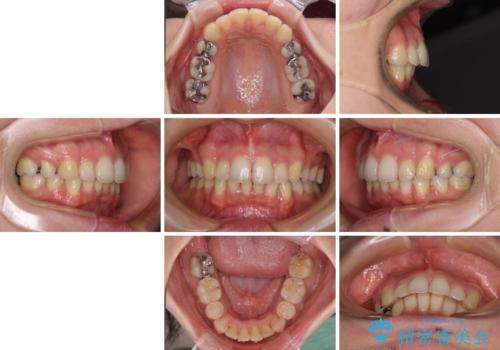

- 上下の出っ歯を気にして来院された患者様です。

口元を積極的に引っ込めるために、上下左右の第一小臼歯を4本抜歯することとしました。

元々ディープバイトのため、スペースを閉じている期間に上下前歯が接触してしまい、治療期間が想定よりも伸びてしまいました。